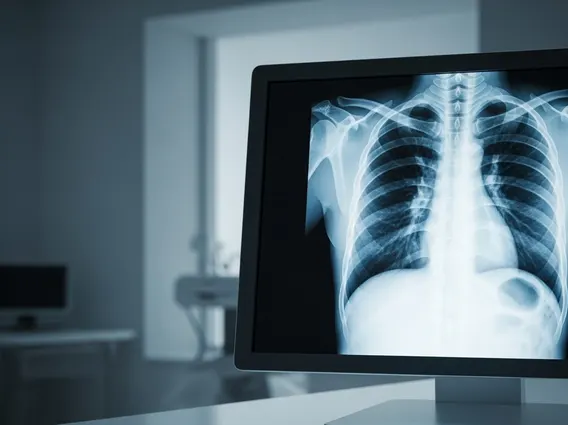

The term Thoracic refers to the chest area of the body, situated between the neck and the abdomen. This critical region is defined by the rib cage, sternum (breastbone), and the vertebral column, specifically the thoracic spine explained as the middle section of the spine, comprising twelve vertebrae (T1-T12). These vertebrae are unique because they articulate with the ribs, forming a protective cage around vital organs. The primary function of the thoracic region anatomy and function centers on protecting the heart and lungs, facilitating respiration, and providing structural support for the upper body.

The thoracic cavity is the space enclosed by the ribs, vertebral column, and sternum, and is separated from the abdominal cavity by the diaphragm. This vital cavity is subdivided into three main compartments: the two pleural cavities, each housing a lung, and the mediastinum, located between the lungs. The mediastinum contains the heart, major blood vessels (aorta, vena cava), trachea, esophagus, and thymus gland. The robust bony framework of the thoracic cavity provides essential protection for these delicate and life-sustaining organs from external trauma.